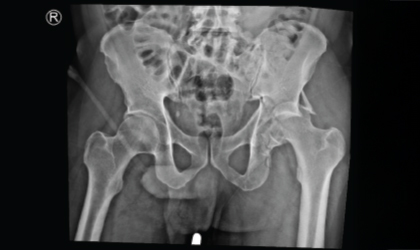

This 62 year old man had a fracture dislocation of his hip following a road traffic accident. He was referred to us two weeks later with a dislocated and fractured hip He underwent fixation of the fracure. The head was damaged and not viable after been dislocated for long. Hence he had a hip replacement as well These is a very complex surgery but he is back on his feet

On arrival, imaging revealed a severely dislocated hip with associated fracture. Due to the delay in treatment, the femoral head was non-viable and showed signs of damage.